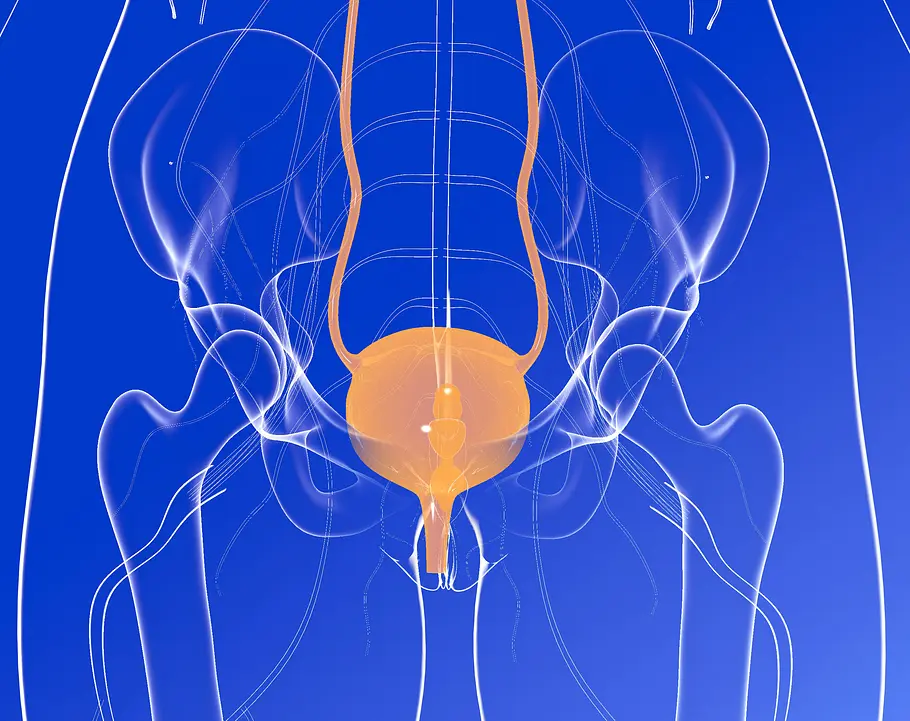

Die Blase ist so etwas wie unser innerer Luftballon. Im leeren Zustand ist sie flach wie eine Scheibe, aber wenn etwas hineinläuft passiert Seltsames. Das und mehr erfährst du hier.

Die menschliche Blase ist unerlässlich, um schnell mal Wasser zu lassen. Doch rund um die Blase gibt es viele seltsame Fakten, die wichtig oder auch mal nicht so wichtig sind - aber trotzdem richtig erstaunlich. Um was es geht, erfährst du hier.

Die Blase - jede Frau kennt sie und leert sie meist mehrmals täglich. Rund um Harndrang, Kapazitäten und Erkrankungen findest du hier 10 Fakten, die teilweise erstaunlich, aber auch seltsam spannend sind.

1. Die Blase ist ein Sammelbecken für rund einen Liter Wasser

Stellt man sich diese Menge einmal bildlich in Form einer 1L-Flasche oder einem Milchkarton vor, ist das tatsächlich ein ziemlich großes Fassungsvermögen für ein inneres Organ.